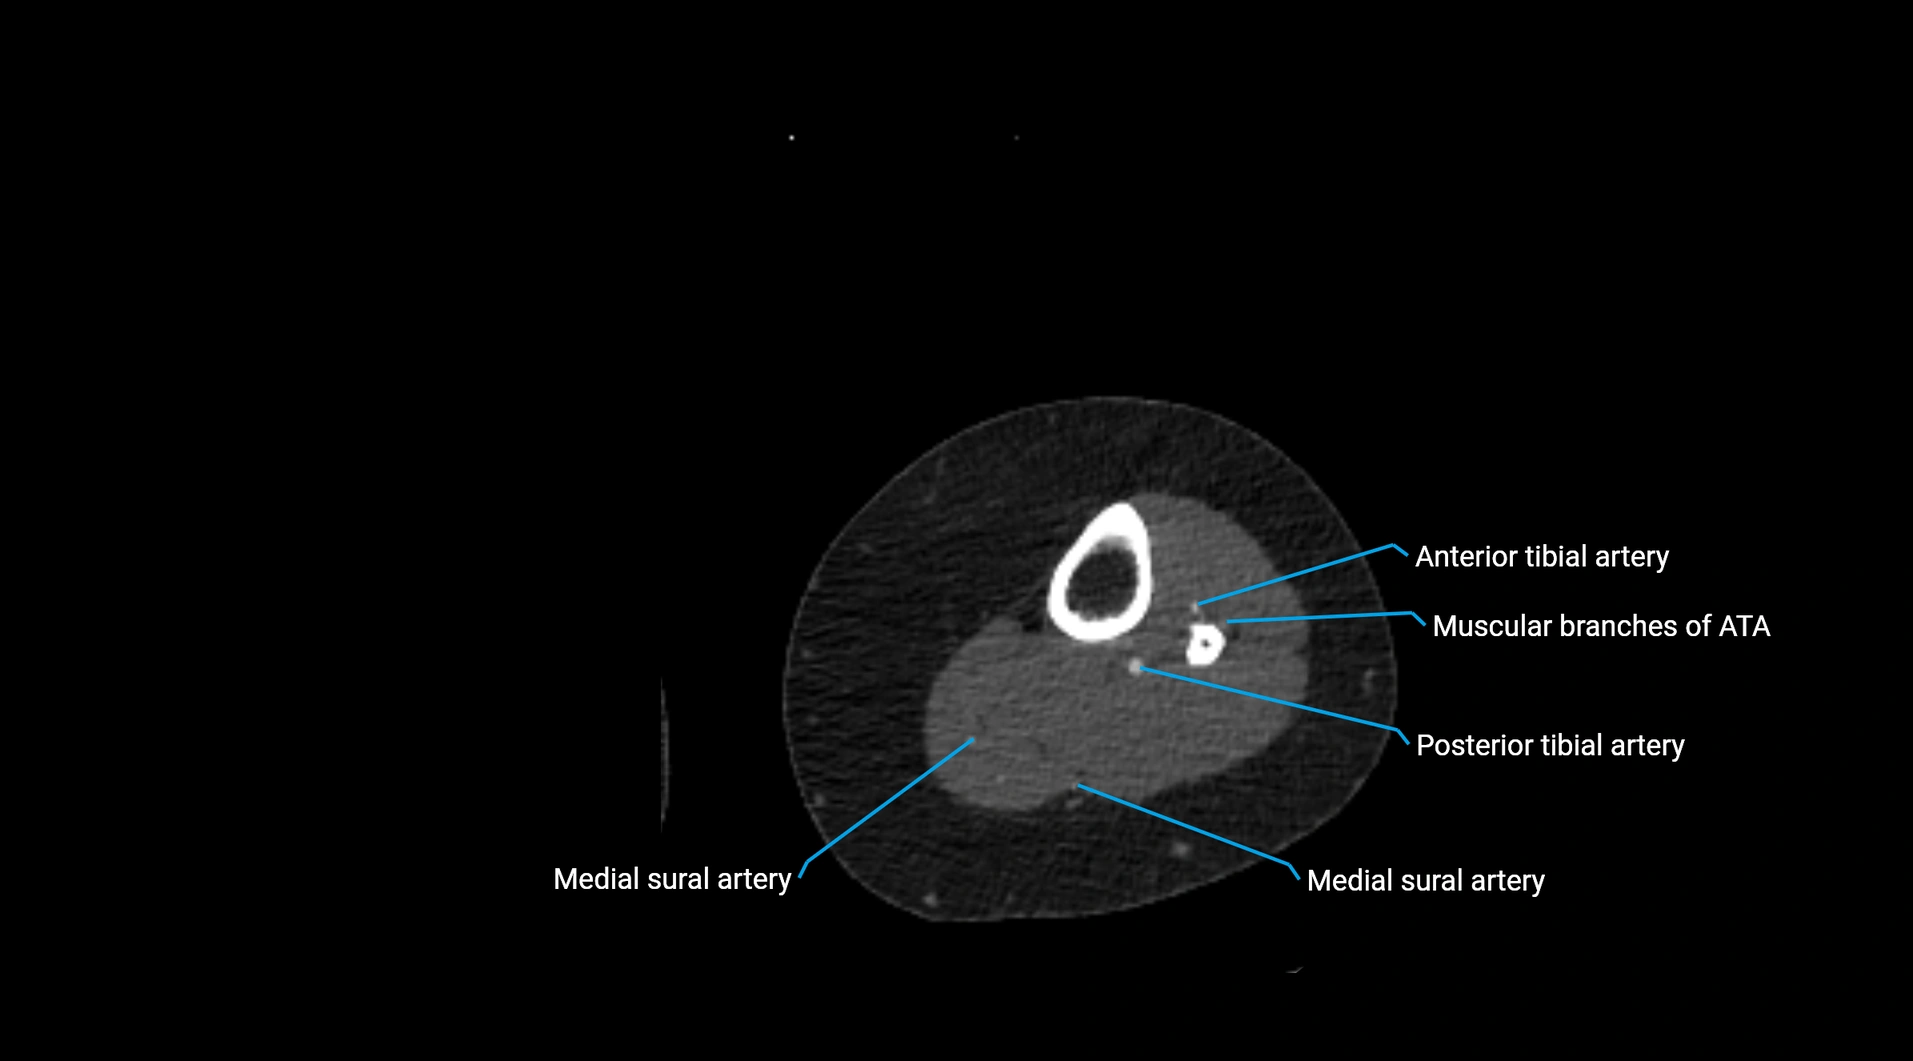

Contrast-enhanced CT (CTA):

• Gold standard for abdominal aortic imaging

• Provides excellent detail of lumen, wall, aneurysm, thrombus, and branch vessels

• Multiplanar and 3D reconstructions help in aneurysm measurement, stent graft planning, and dissection evaluation